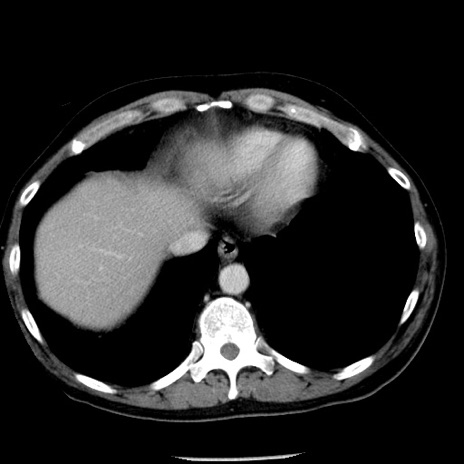

冠状断像

【症例】40歳代男性

【現病歴】2日前から胃痛あり。徐々に周期的な激痛に変化した。本日になっても激痛があるため受診。

【身体所見】意識清明、BT 38-39℃台あり、腹部:膨満、やや硬、右下腹部に圧痛あり。

【データ】WBC 8500、CRP 23.26